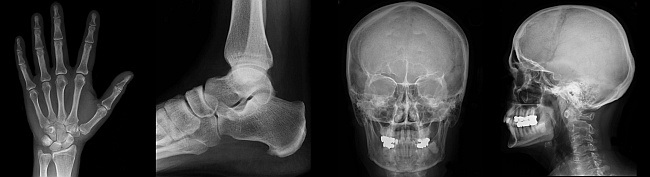

Do you know a mechanical engineer and physicist by the name of Wilhelm Conrad Röntgen? Well, maybe you should! It is because of his genius that we are now able to use X-rays at the doctors! On the 8th of November 1895 Röntgen produced and detected electromagnetic radiation in a wavelength range known as X-rays or Röntgen rays, an achievement that earned him the first Nobel Prize in Physics in 1901. Since Röntgen's discovery that X-rays can identify bone structures, X-rays have been used for medical imaging. The first medical use was less than a month after his scientific paper on the subject and until 2010, 5 billion medical imaging studies have been conducted worldwide. Medical uses include radiographs, computed tomography, fluoroscopy and radiotherapy.